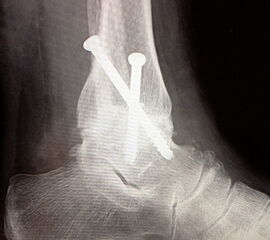

Fixation mit mindestens 2, ggf. 3 kanülierten Schrauben (6,0, 6,5 oder 7,0 mm), die von medial-kranial und lateral-kranial nach kaudal oder von anterior-kranial nach posterior-distal (Abb. 6) in den Talus unter BV-Kontrolle in 2 Ebenen eingebracht werden (Sabo 2014). Im amerikanischen Sprachraum ist die Verwendung der von dorsal-lateral paraachillär nach anterior-medial in den Corpus tali gerichteten Zugschraube geläufig („home run-screw“) (Abb. 7). Es ist darauf zu achten, das untere Sprunggelenk nicht mit Schrauben zu perforieren. Idealerweise spannen die Kompressionsschrauben, deren Gewindegänge nur im Talus liegen sollten diesen stabil in die Malleolengabel ein.

Abbildung 1b